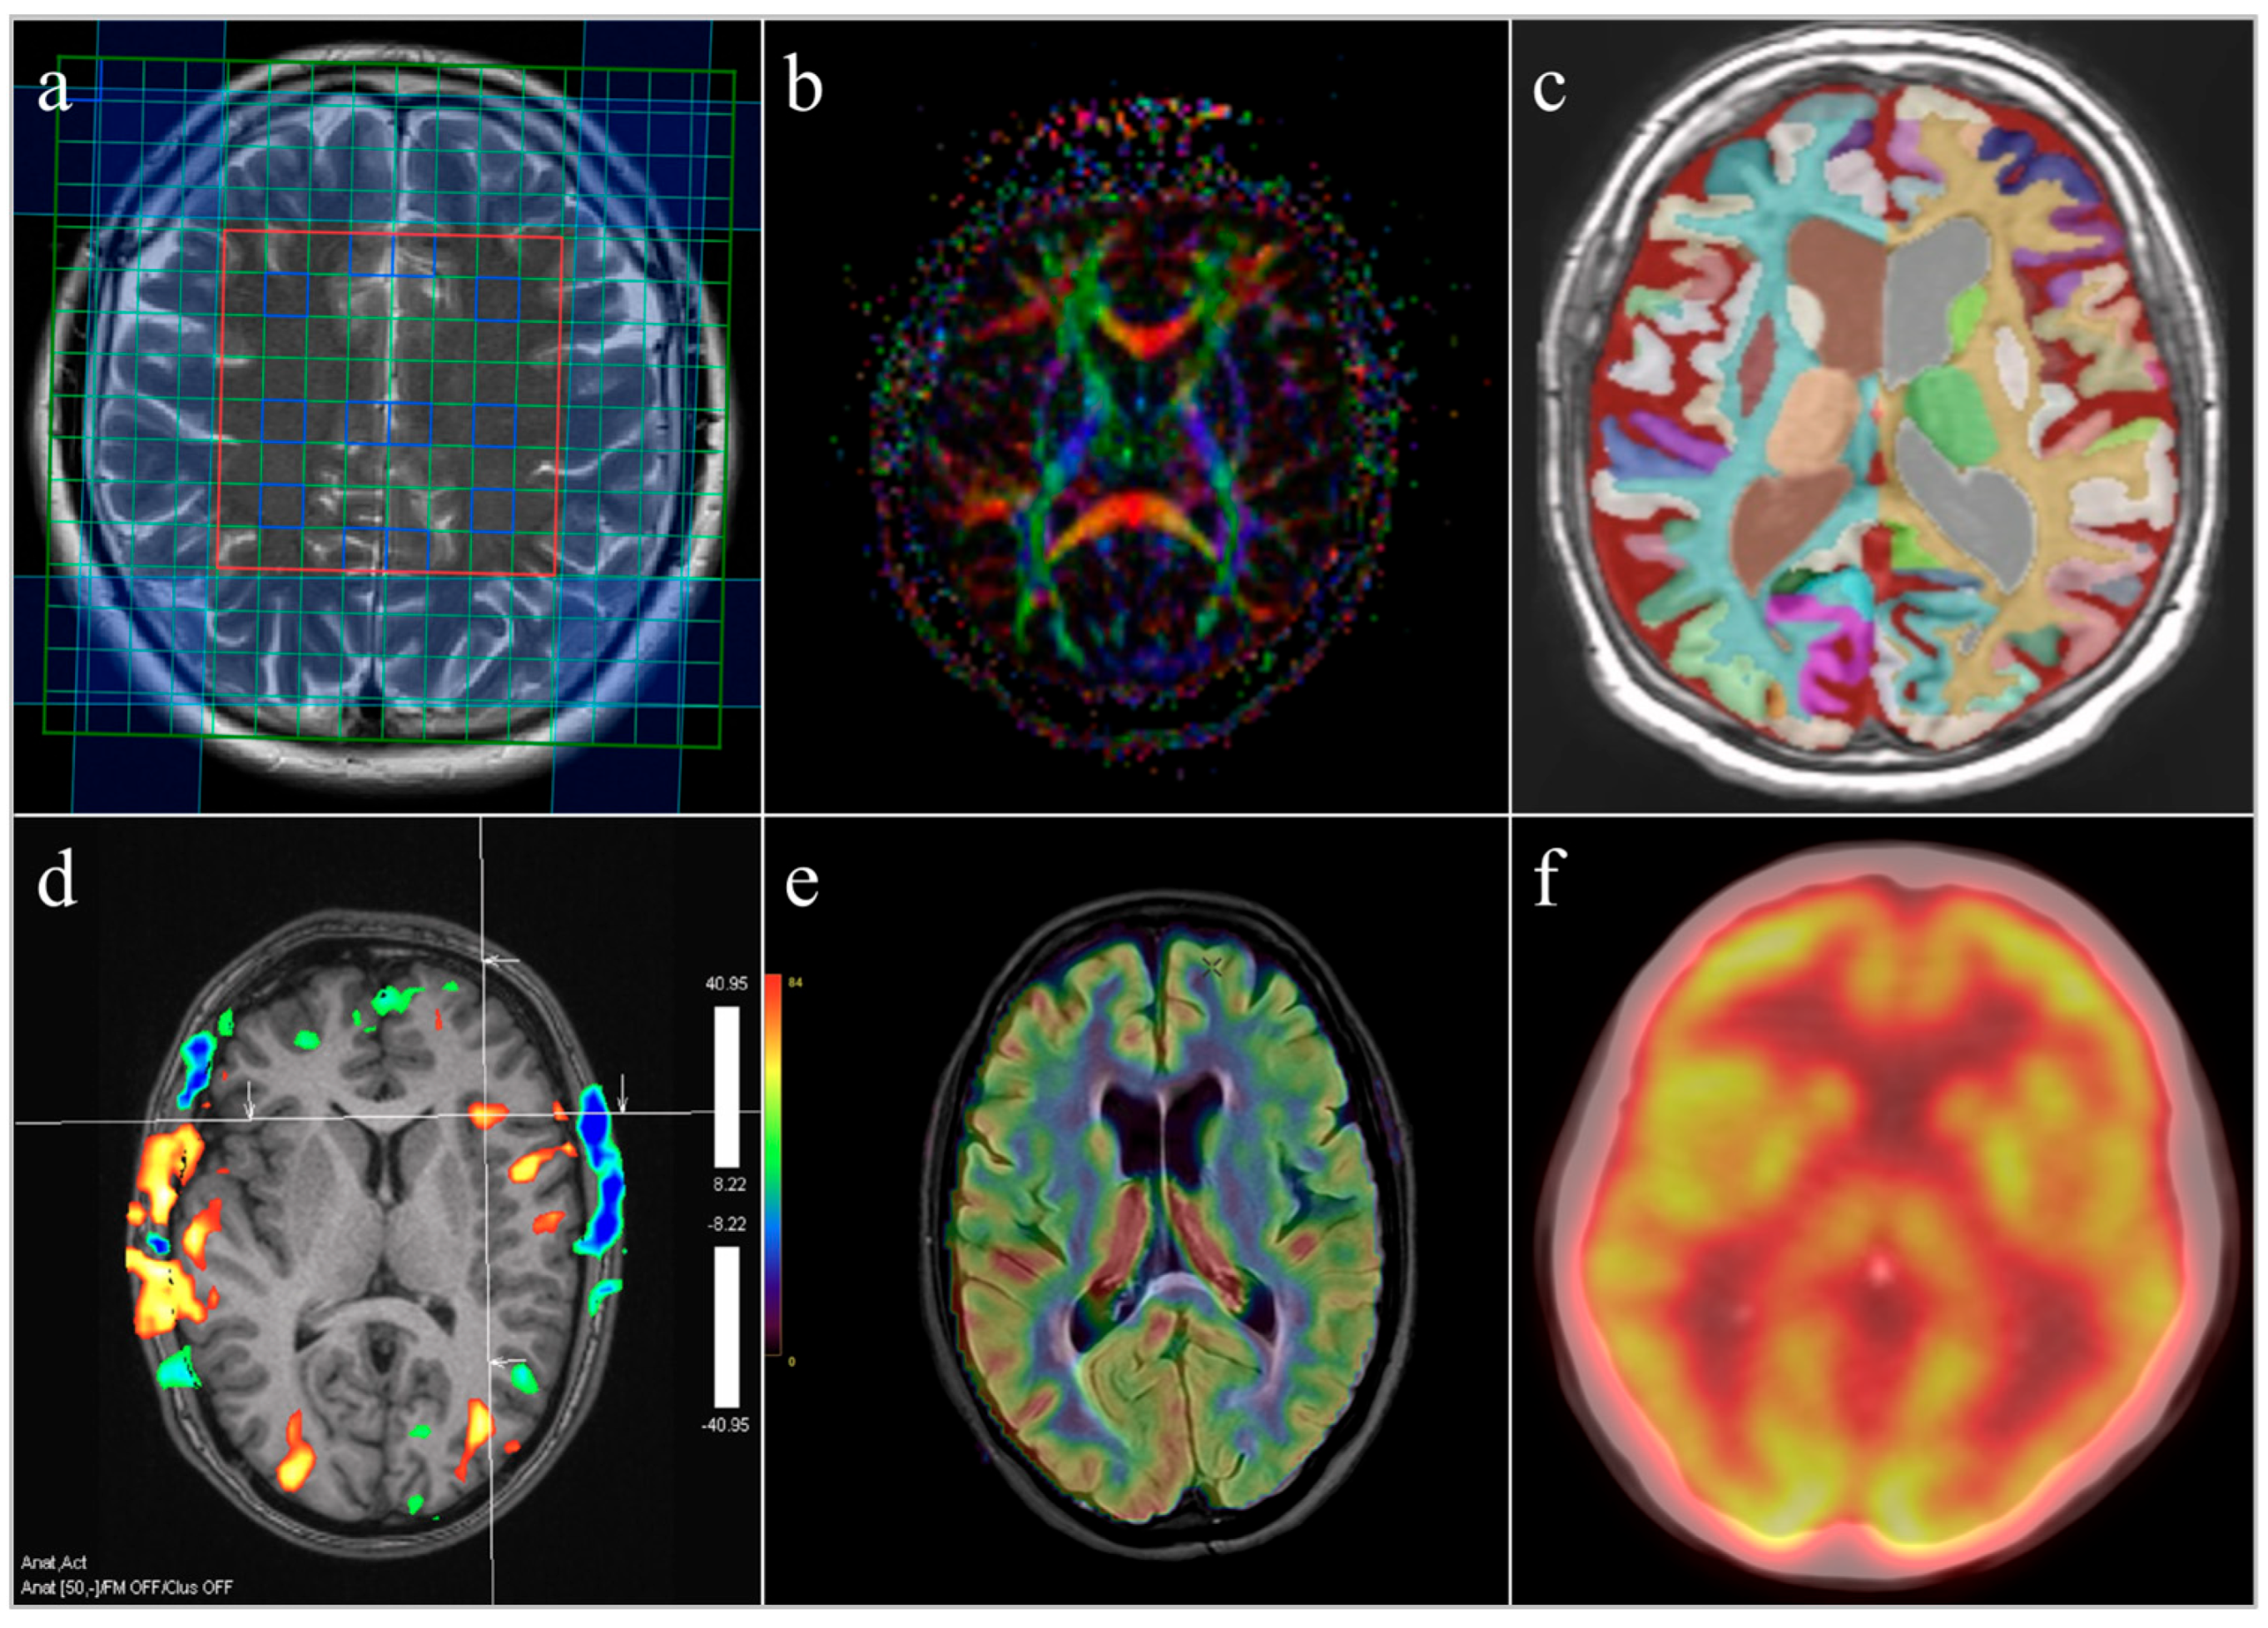

7. Magnetic Resonance Spectroscopy as a Tool for Assessing Obesity-Related Brain Vulnerability

8. Complementary Neuroimaging Biomarkers Beyond MRS

8.1. Diffusion Tensor Imaging and Glymphatic Dysfunction

8.2. Volumetric MRI and Cardiometabolic Mediation

8.3. Functional MRI and Network-Level Alterations

8.4. Cerebral Perfusion Imaging and Neurovascular Dysfunction

8.5. Positron Emission Tomography and Molecular Targets